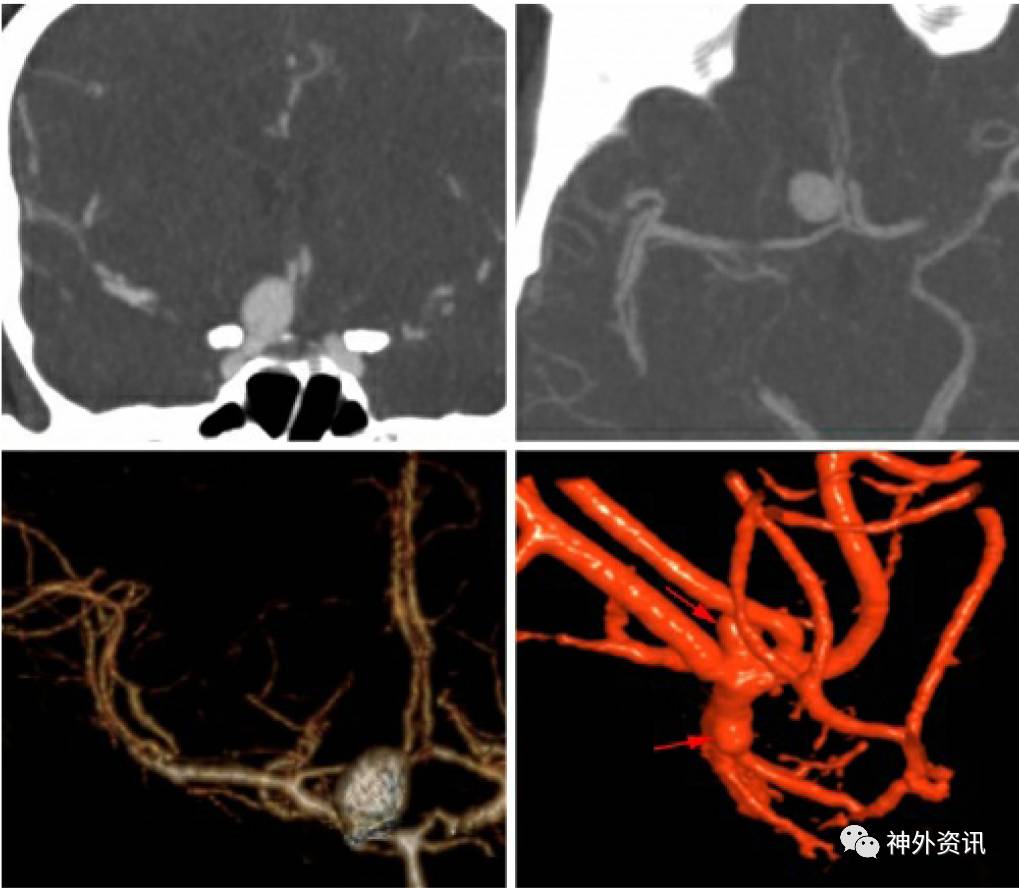

图2. 本例患者CTA提示前交通动脉瘤,术后血管造影复查时却发现一枚同侧大脑中动脉瘤(再次回顾首次CTA图像时该动脉瘤疑似可见),因此又进行了第二次手术夹闭这枚大脑中动脉M1段动脉瘤。

上述病例说明了CTA对检测小动脉瘤(直径<4mm)的局限性,尤其是位于拥挤的侧裂池内(的动脉瘤)。因为这些患者既往因其他动脉瘤破裂发生过SAH,所以这些小动脉瘤是需要处理的,而术后造影对它们的延迟发现则导致了不必要的二次手术。